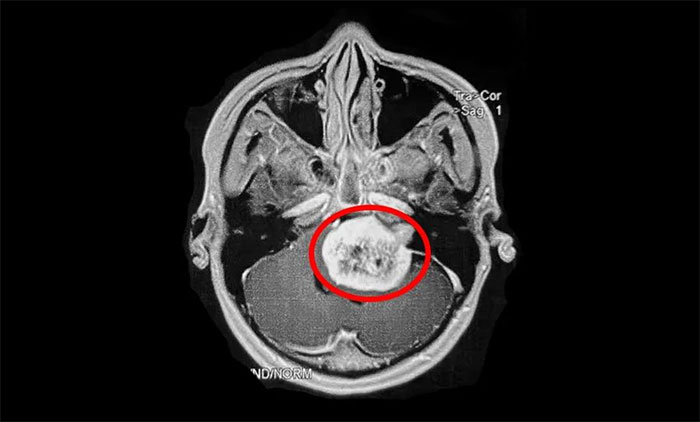

早诊断、早治疗是关键

值得注意的是,听神经瘤早期表现易与耳聋及其他一些颅脑肿瘤混淆,出现相应症状时,患者应及早到具备专科诊疗能力的医疗机构,通过听力学检查、面神经功能检查、前庭功能检查、影像学检查(听神经瘤主要检查手段),即可明确诊断。

▲ 影像学检查是听神经瘤主要检查手段(示意图)

听神经瘤的治疗并非易事。对于已生长较大及已出现症状的肿瘤,治疗策略包括手术治疗和立体定向放射治疗,选择取决于肿瘤分期、位置、生长速度、是否囊性变、患侧及对侧听力水平、患者年龄、身体状况等。其中,手术是听神经瘤主要治疗方式。